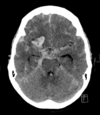

Which vessel is most likely to have ruptured? Left anterior cerebral artery Right anterior cerebral artery Left middle cerebral artery Right middle cerebral artery

The **right middle cerebral artery** is the most likely to have ruptured in this scenario, as this travels out laterally to supply the lateral region of the cortex.

What symptoms might the patient experience? [2]

The haemorrhage is in the region of the right middle cerebral artery **Left-sided upper limb paraesthesia** and **left-sided upper limb weakness.** Aphasia is less likely in this case, as Broca’s area (responsible for expressive speech) is most commonly found on the left hemisphere, along with Wernicke’s area (responsible for receptive speech).